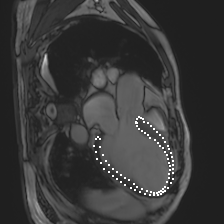

Accurate segmentation and motion estimation of myocardium have always been important in clinic field, which essentially contribute to the downstream diagnosis. However, existing methods cannot always guarantee the shape integrity for myocardium segmentation. In addition, motion estimation requires point correspondence on the myocardium region across different frames. In this paper, we propose a novel end-to-end deep statistic shape model to focus on myocardium segmentation with both shape integrity and boundary correspondence preserving. Specifically, myocardium shapes are represented by a fixed number of points, whose variations are extracted by Principal Component Analysis (PCA). Deep neural network is used to predict the transformation parameters (both affine and deformation), which are then used to warp the mean point cloud to the image domain. Furthermore, a differentiable rendering layer is introduced to incorporate mask supervision into the framework to learn more accurate point clouds. In this way, the proposed method is able to consistently produce anatomically reasonable segmentation mask without post processing. Additionally, the predicted point cloud guarantees boundary correspondence for sequential images, which contributes to the downstream tasks, such as the motion estimation of myocardium. We conduct several experiments to demonstrate the effectiveness of the proposed method on several benchmark datasets.